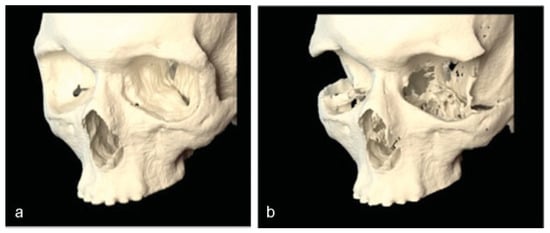

Three months after the decompression, the patient had a postoperative helical CT study. The postoperative imaging demonstrated the bony removal and decompression of the orbital soft tissues (Figure 5). Virtual stereolithographic models were generated from the DICOM data and used for direct comparison of the pre- and postoperative orbits (Figure 6).

Three-month postoperative imaging demonstrated the bony removal and decompression of the orbital soft tissues (Figure 10). Virtual stereolithographic (Figure 11) and three-dimensional volumetric models were generated from the DICOM data and used for direct comparison of the pre- and postoperative orbits.

Figure 6. Virtual stereolithographic rendering before (a) and after (b) decompression for patient 1.